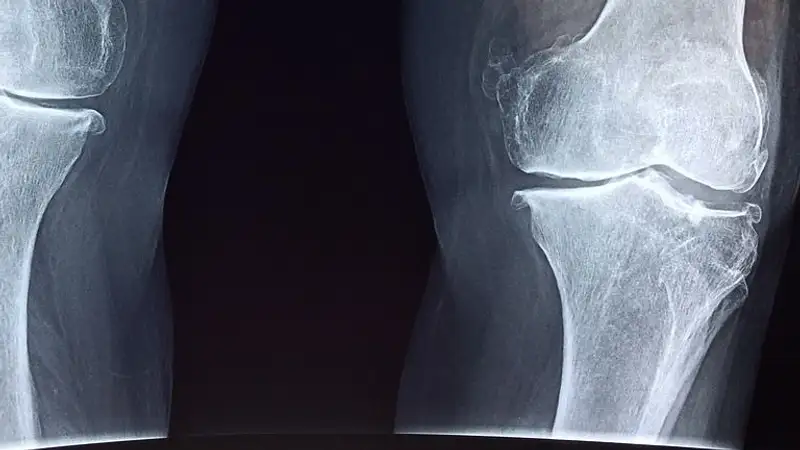

Ученые Питтсбургского университета открыли новую возможность для сращивания костей, применяя устройство, схожее с проволокой для брекетов, сообщает Zakon.kz.

Как сказано в научном материале, изучение новой технологии проходило на мышах. Для сращивания поврежденных костей черепа авторы использовали устройство, напоминающее ортодонтическую проволоку для выравнивания зубов. Исследователи установили систему вдоль швов черепа грызуна, у которого были серьезные повреждения. Система активировала скелетные стволовые клетки черепа, что привело к заживлению костей.

При эксперименте не были использованы биоматериалы или импланты, отмечено в исследовании. Кости сращивались за счет собственных стволовых клеток.

Ученые подчеркивают, что удачным оказался эксперимент среди мышей, чей возраст можно сравнить с молодым возрастом людей. У мышей более старшего поколения подход не сработал. Ученые объясняют это тем, что у взрослых мышей меньшее количество стволовых клеток в организме.